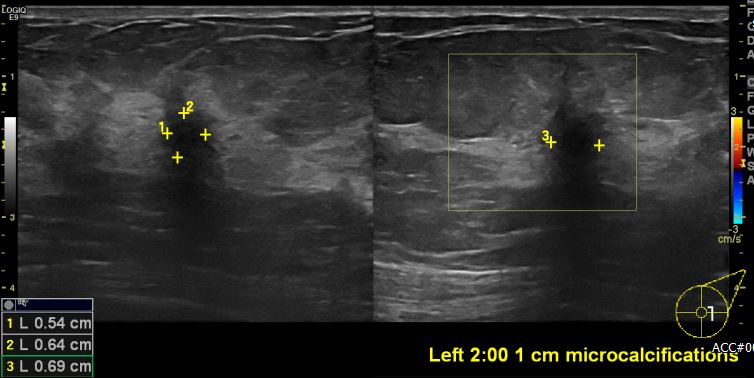

상기환자 건강검진상 이상 소견으로 내원하신 60대 여성분으로 좌측 2시 방향에서

1cm 떨어진 거리의 미세석회 포함된 의심스러운 멍울 조직검사 시행하여 좌측 유관암

진단 되었습니다.